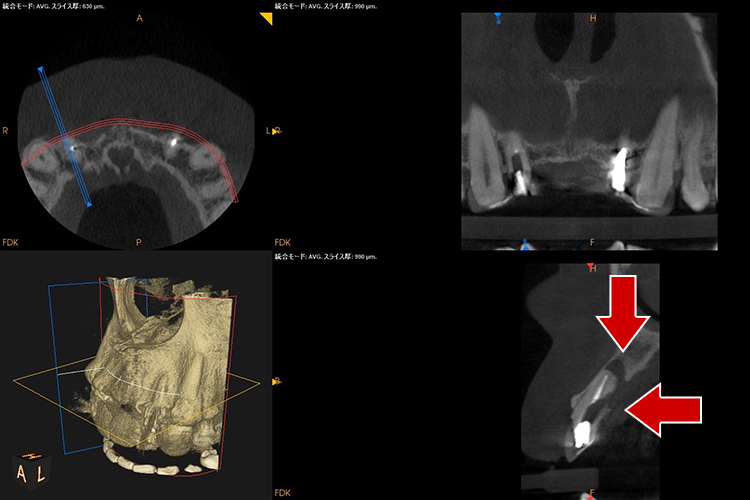

診査・診断・カウンセリング根管治療 を行なう歯の診査はいろいろあり、当院ではレントゲン撮影、CT撮影、触診、打診、神経の生活度の診査、歯周ポケット検査から歯の状態を診査します。個々の歯によって病気の状態は様々です。治療の難易度、予後、治療に伴うリスク、治療期間、費用などをご説明していきます。当院で治療を行う歯には、通常の二次元画像のレントゲンでは診断が難しい場合、または、治療にあたって歯根の形を詳細に把握し、根管の形に適したサイズの器具を選択するため、根管治療専用の高精細モードのCBCT 撮影を行うことがほとんです。 当院のCBCT は根管治療専用モードのため撮影範囲が最小です。インプラント用CTのような撮影範囲が大きい機種よりも被曝量が少なく、無駄な被曝がないよう配慮しています。 |

超最難関case(根尖病巣+パーフォレーション(術者のミス)

通常は「抜歯が当然」のcaseですが抜歯なしで治療成功事例

右下の画像が一番変化を診る上で基準となる画像でして(CT)、根の先端の病気が減っていること、白く濃く映った根のお薬がしっかりと入っている事が分かると思います。根の途中の黒い穴は、最初のドクターが謝って穴をあけてし合った後です。こういった高度な治療もセカンドオピニオンとしてお受けしております。

治療前

治療中

治療1年後

治療後3年後

レントゲンで施術前と施術後の比較

・赤色の部分→ドクターのミスをした箇所になります「パーフォレーション」

→結果、、、そこから病気ができています。。。

→通常はこれだけで「抜歯」となります。。。

・黄色の部分が根尖の病巣です。

→この原因でも抜歯となることもあります。

こちらの症例に関しても抜歯するくこともなく、治療成功となります。